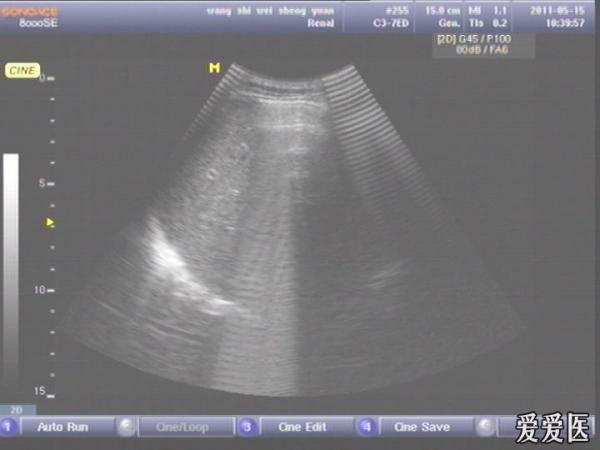

患者,男,38岁,进食后突发上腹部持续性剧烈疼痛一小时来查。超声见横膈与肝之间、上腹部皮下气体强反射回声,后伴多重反射,肝前、肝肾间隙,腹腔肠管间均可见游离无回声区。直视腹部见上腹部似板样。结合病史提示“胃肠道穿孔”。急诊手术证实。